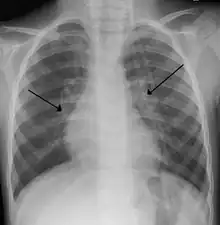

X-ray of a child with RSV bronchiolitis showing the typical bilateral perihilar fullness

Chest X-ray findings in children with RSV bronchiolitis are generally nonspecific and include perihilar markings, patchy hyperinflation, and atelectasis.[20] However, the American Academy of Pediatrics (AAP) does not recommend routine imaging for children with presumed RSV bronchiolitis because it does not change clinical outcomes and is associated with increased antibiotic use.[20][5] Chest X-ray is sometimes considered when the diagnosis of bronchiolitis is unclear or when there is an unexpected worsening.[5] In adults with RSV infection, chest films are often normal or demonstrate nonspecific changes consistent with viral pneumonia, such as patchy bilateral infiltrates.[44]